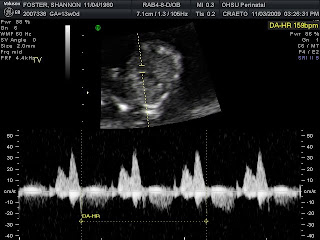

Not much of a baby bump yet at 16 1/2 wks.